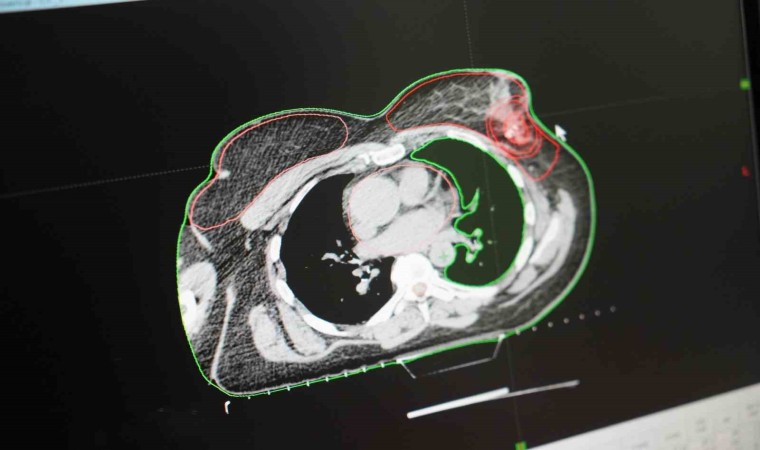

Meme kanserinde radyoterapinin önemine değinen Radyasyon Onkolojisi Uzmanı Dr. Özge Özdemir ise, “Meme kanseri, kadın kanserlerinin 3’te 1’ini oluşturmaktadır. Bu nedenle farkındalık önem arz ediyor. Radyasyon onkologları olarak tedavinin her aşamasında hastaların yanındayız. Hem cerrahi hem kemoterapi hem de radyoterapi bir ekip olarak işbaşındayız. Meme kanserinin radyoterapisini erken evrede meme koruyucu cerrahi yapılmış olgularda daha sonra meme ve lenf bölgesine vaka kontrolü sağlamak yani nüksleri engellemek ve hastanın sağ kalımını sağlamak amacıyla uygulamaktayız. Yine lokal ileri hastalıkta sistemik kemoterapi sonrası uygulanan cerrahinin ardından nüksleri engellemek ya da kemoterapi sonrası cerrahi uygun olmayan vakalarda tümörü küçültmek amaçlı radyoterapi yapıyoruz. Ayrıca beyin metastazlarında, kemik metastazlarında ağrıyı gidermek, yumuşak doku metastazlarında kitlenin ağrısını, kanamasını, kokusunu gidermek amaçlı da palyatif radyoterapi yapmaktayız. Meme kanserinde radyoterapi her aşamada olmazsa olmaz bir yaklaşımdır. Radyoterapi alanındaki bilimsel ve teknolojik gelişmeler sayesinde hedeflediğimiz dozu uygulayacağımı volume uygun, yan etki profili en az olacak şekilde uygulayabilmekteyiz. Bu açıdan radyoterapi güvenilir bir tedavi yöntemidir. Meme kanseri farkındalığı hayatımızda olsun ama meme kanseri hayatımızda olmasın” diye konuştu.